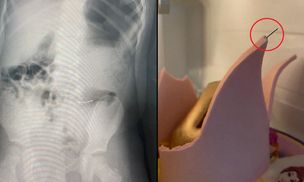

W urodzinowym torcie były metalowe szpilki. Dwoje dzieci trafiło do szpitala